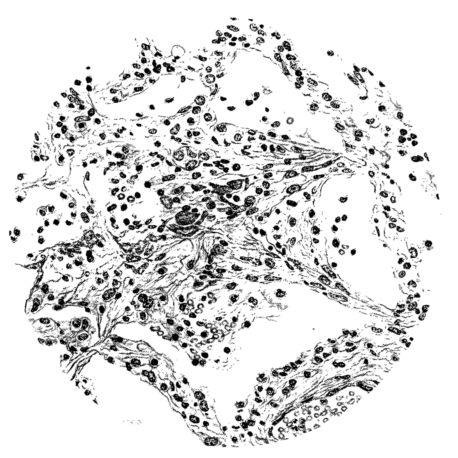

The changes are less marked, perhaps, in the trachea than in its finer ramifications. The mucosa is constantly more or less destroyed and large areas, usually focal, are entirely devoid of their epithelial covering. This is replaced by a sparse exudate, composed largely of red blood cells, mucus, a small amount of fibrin, and nuclear fragments (Fig. II). It may dip into the submucosa for a short distance, but usually these indentures are associated with the ducts of the mucous glands into which the inflammatory reaction extends. A more striking feature than the exudate, however, is the edema and the congestion of the submucosa. The loose areolar tissue of the submucosa is spread widely apart, and throughout it distended blood vessels are very conspicuous. Occasionally such a vessel is broken and actual hemorrhage appears in the submucosa. Occasionally, too, the inflammation extends down the duct to the mucous gland itself, and here, also, aplastic inflammatory reaction is evident, inasmuch as the acini now stain intensely red with the cells undifferentiated from each other and specked here and there by broken remains of the dead nuclei (Fig. III). After the disease has continued for a short period, even at the end of five or six days, some regeneration of the epithelial lining may be seen (3) (Fig. IV). But despite this, the acute picture persists, and there goes on, side by side, an attempted repair characterized by epithelial regeneration and the same evidence of acute change. Since the lesion is essentially a superficial one, scars or contractures of any extent are not encountered in the trachea, even in examples of the disease that have ended fatally only after many weeks.[4]

FIG. VIII. AUTOPSY NO. 97. ALTHOUGH THE EPITHELIUM IS STILL VISIBLE AS A HYALINE BAND LIFTED FROM THE UNDERLYING MUCOSA, BOTH MUCOSA AND SUBMUCOSA ARE INVOLVED IN A NECROTIZING PROCESS. BACTERIA ARE ABUNDANT IN THE DEAD TISSUE.